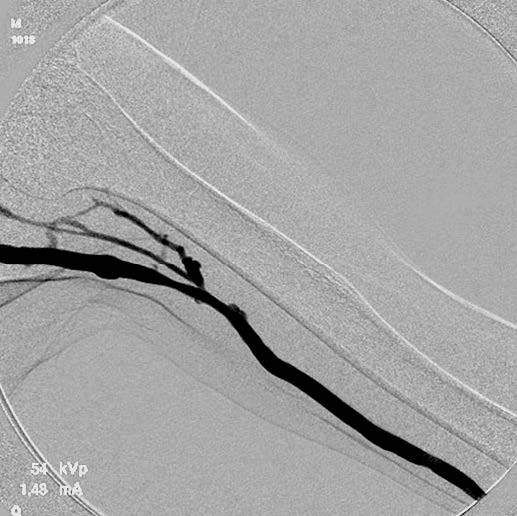

血栓除去+バルーン拡張: 人工血管を切開し、エコーガイド下にて4 Fr血栓除去カテーテルを用いて人工血管内の血栓を除去した。血流再開後のエコーで人工血管流出路静脈の高度狭窄を認めたため、人工血管に6Frシースを挿入して血管造影で確認したのち(図1)、6 mmのコンクエスト®*を用いて病変部を拡張した。最大30気圧まで加圧し、バルーンの完全拡張を得たが、PTA 後の血管造影でエラスティックリコイルを認めた(図2)。